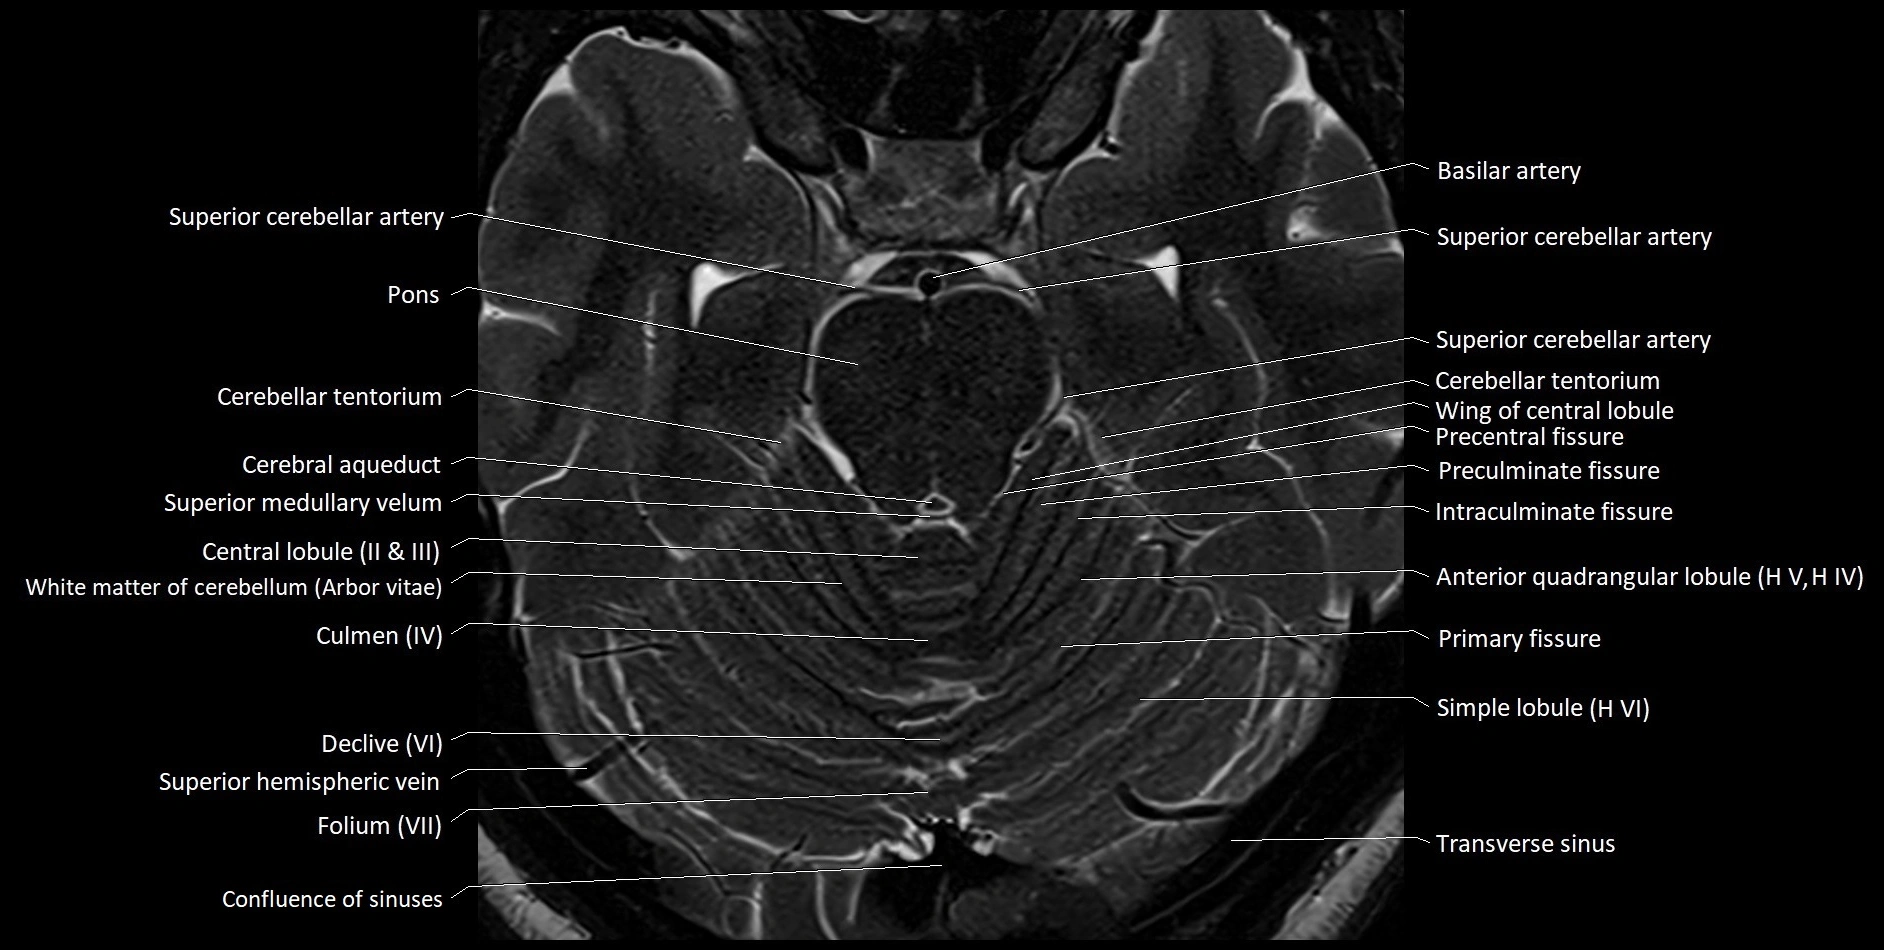

MRI images